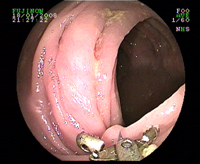

Poussée de rectocolite hémorragique

Ulcères du rectum sur rectocolite hémorragique

Ulcérations coliques de rectocolite hémorragique